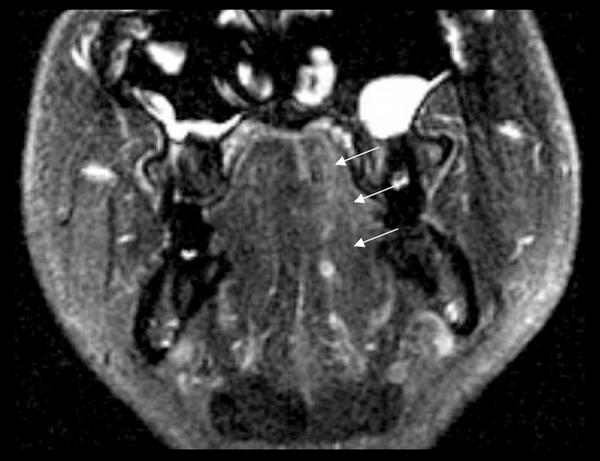

BACKGROUND Isolated unilateral hypoglossal nerve injury is extremely rare. It may be caused by radiation therapy targeting neoplasms of the cephalic region. CASE REPORT A 51-year-old man with synovial sarcoma of the left upper arm status post extensive radiation therapy in 1980 presented in late 2014 with gradual onset of speech difficulty and difficulty moving his tongue for a couple of weeks. Neurological examination revealed isolated left-sided unilateral tongue atrophy. Postradiation residual extensive cicatrix with erythema over the whole left upper extremity extending to the neck on the affected side was noticed. On head magnetic resonance imaging (MRI) before and after administration of gadolinium, he was found to have asymmetrically fatty striations, atrophy, and fibrosis in the left tongue consistent with radiation toxicity. The patient's tongue weakness persisted without improvement. CONCLUSIONS The diagnosis of unilateral hypoglossal nerve injury is usually difficult. Detailed neurological examinations and thorough investigations including head MRI are very helpful. Previous exposure to radiation therapy is a potential cause of hypoglossal nerve injury. To our knowledge, this is the first case report that presents isolated unilateral tongue atrophy as a late complication of juxta cephalic radiation therapy.

孤立性单侧舌下神经损伤极为罕见。它可能由针对头颈部肿瘤的放射治疗引起。病例报告:一名51岁男性,1980年因左上臂滑膜肉瘤接受广泛放射治疗,2014年末出现渐进性言语困难及数周来舌运动困难。神经系统检查发现孤立性左侧单侧舌萎缩。注意到放疗后残留广泛瘢痕,整个左侧上肢包括患侧颈部出现红斑。在钆剂增强前后的头部磁共振成像(MRI)检查中,发现其左侧舌部存在不对称性脂肪条纹、萎缩及纤维化,符合放射毒性表现。患者的舌肌无力持续存在且无改善。结论:单侧舌下神经损伤的诊断通常较为困难。详细的神经系统检查以及包括头部MRI在内的全面检查非常有帮助。既往接受放射治疗是舌下神经损伤的一个潜在原因。据我们所知,这是首例将孤立性单侧舌萎缩作为头颈部放疗晚期并发症的病例报告。